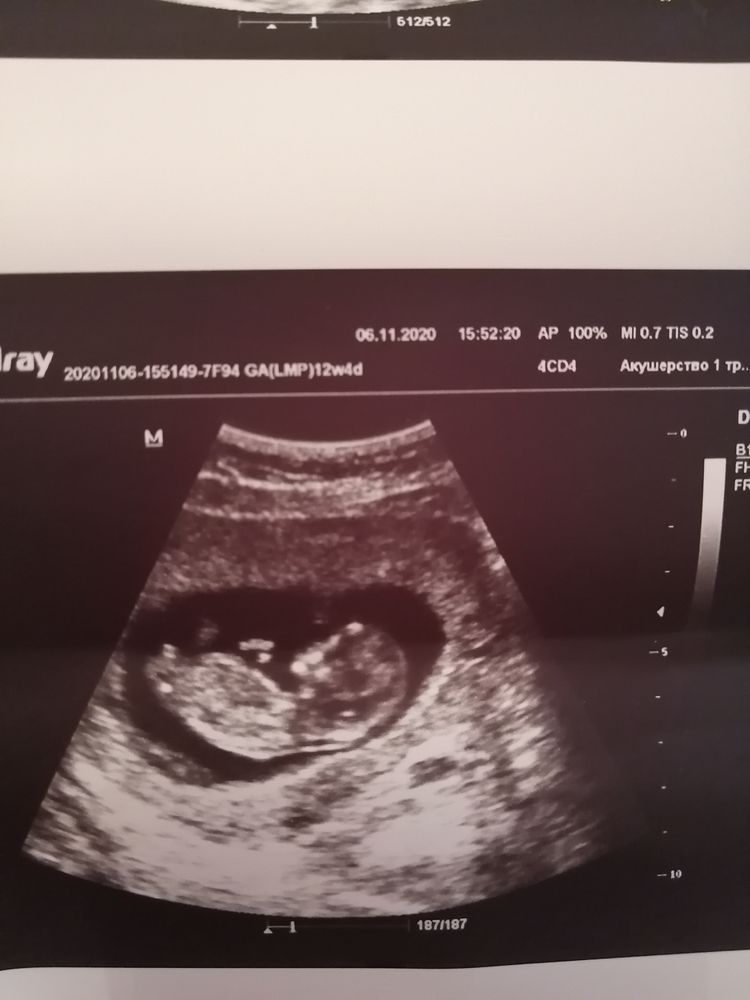

12 неделя 4 дня

Пол малышаДд девочки! 11 недель была угроза, отслойка приличная. Пролежала на сохранении 5 дней. Сегодня была в узи говорит будет мазать коричневым. Надо не лежать а ходить. Надеюсь все будет хорошо. Пол ребеночка не сказала. У некоторых уже говорят. Как думаете кто у нас?? У нас тут много опытных мамочек)))